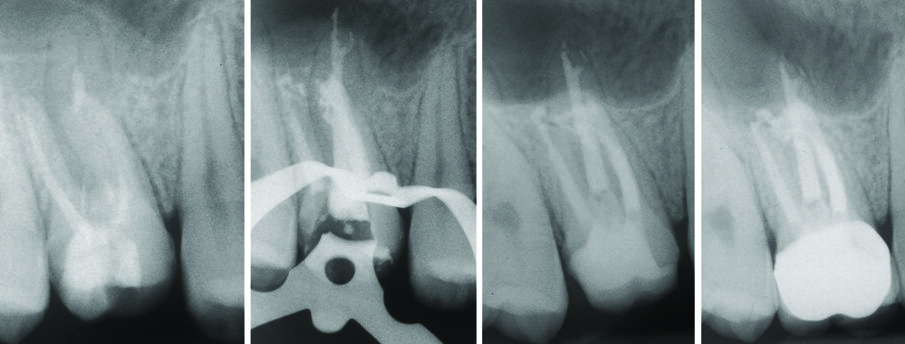

All’esame radiografico le otturazioni appaiono dense ed omogenee, la guttaperca mostra un buon adattamento alla morfologia endodontica, determinando un buon riempimento delle irregolarità del sistema canalare. Sono stati evidenziati la presenza di canali laterali ed uscite apicali multiple. Figg. 8a-8e molare superiore, Figg. 9a-9e molare inferiore, Figg. 10a-10c molare superiore, Figg. 11a-11d anatomie complesse premolare curvo e Figg. 12a-12d ottavo.

Fig. 9 - Ritrattamento canalare 3.7 controllo a 7 anni.

Fig. 10 - Terapia canalare 1.5 doppia curva il canale preparato manualmente con Mtwo.